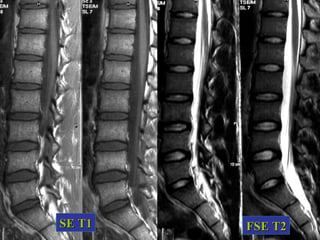

NORMAL

• Disco jovem sem alterações degenerativas.

SE T1   FSE T2

Terminologia das alterações degenerativas

da coluna vertebral

• DISCO INTERVERTEBRAL

DESIDRATAÇÃO DISCAL

•    da quantidade de água no núcleo

pulposo e alterações nas proporções

dos níveis de proteoglicans

• RX, CT e RM -    da altura do disco,

calcificação ou gás

• RM – perda do hipersinal em T2